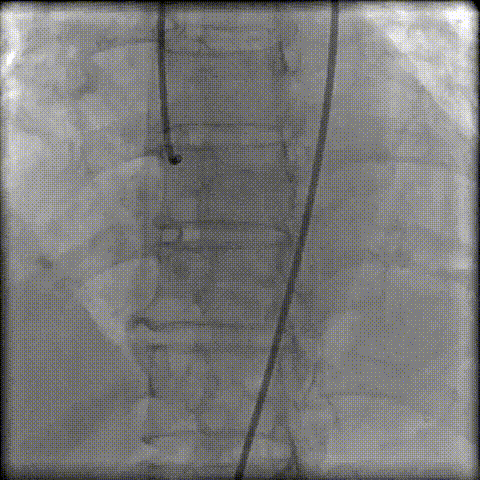

术前冠脉评估

“右足”+“左头”根部造影评估